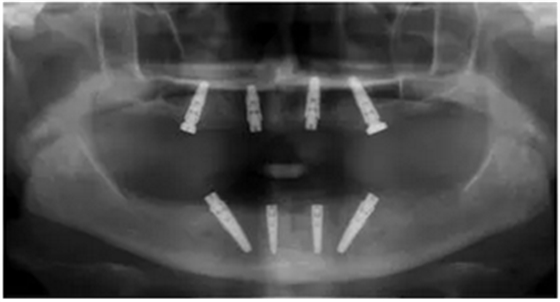

手術(shù)后90天拍攝連帶內(nèi)錐形連接愈合基臺的X光片。

手術(shù)后16周最終修復(fù)X光片:計算機(jī)輔助導(dǎo)板引導(dǎo)種植能夠保證在All-on-4治療中精準(zhǔn)安全地植入軸向和傾斜植體。